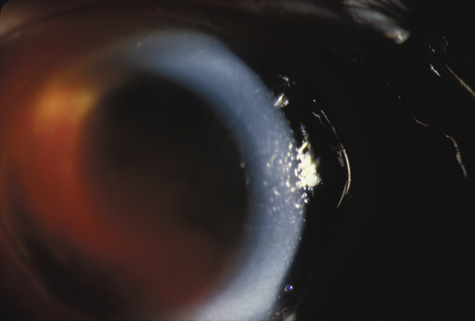

When the cornea is abruptly forced backward by severe blunt trauma, it presses the iris against the lens, preventing the escape of aqueous into the posterior chamber. If enough force is applied, the entrapped aqueous dissects into the ciliary body, resulting in a recessed angle (Fig. 4). This tearing of the ciliary body is responsible for approximately 90% of the hyphemas seen after blunt trauma.31,32 Other causes of hemorrhage include separation of the iris from the ciliary body (iridodialysis) and sphincter tears. Ultrasound biomicroscopy can be useful in diagnosing dissection of the ciliary body or iridodialysis (Fig. 5).33–35

Fig. 4. Angle recession after blunt trauma.